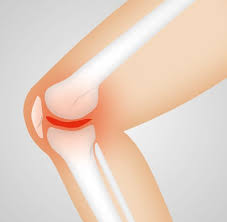

- 관절염: 노화 또는 부상으로 인해 연골이 소실되어 발생하는 관절염은 무릎에 통증을 유발할 수 있습니다.

관절염은 무릎 구부릴 때 통증의 가장 흔한 원인 중 하나입니다. 나이가 들면서 무릎 관절의 연골이 마모되고, 이는 통증과 염증을 유발합니다. 관절염은 퇴행성 변화로 인해 발생하는 경우가 많으며, 일반적으로 노인에게서 더 많이 나타납니다. 관절염으로 인한 통증은 구부릴 때 더욱 심하게 느껴질 수 있으며, 이는 일상적인 활동에 큰 지장을 줄 수 있습니다.

- 부기: 염증이나 부상으로 인해 무릎이 부풀어 오르는 경우가 많습니다. 부기는 통증과 함께 나타나는 경우가 많습니다.

- 소리: 무릎을 구부릴 때 '딱딱'하거나 '끼익'하는 소리가 들리는 경우도 있습니다. 이는 관절의 마모나 손상을 시사할 수 있습니다.